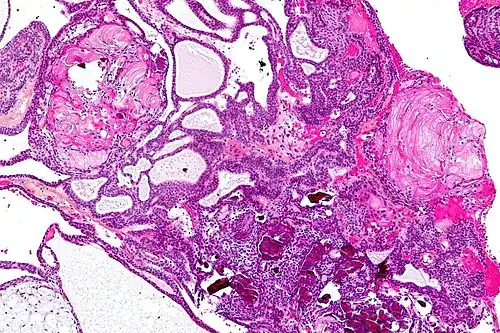

On macroscopic examination, craniopharyngiomas are cystic or partially cystic with solid areas. On light microscopy, the cysts are seen to be lined by stratified squamous epithelium. Keratin pearls may also be seen. The cysts are usually filled with a yellow, viscous fluid rich in cholesterol crystals. Of a long list of possible symptoms, the most common presentations include headaches, growth failure, and bitemporal hemianopsia.

Micrograph showing the characteristic features of an adamantinomatous craniopharyngioma - cystic spaces, calcifications, and "wet" keratin, HPS stain -